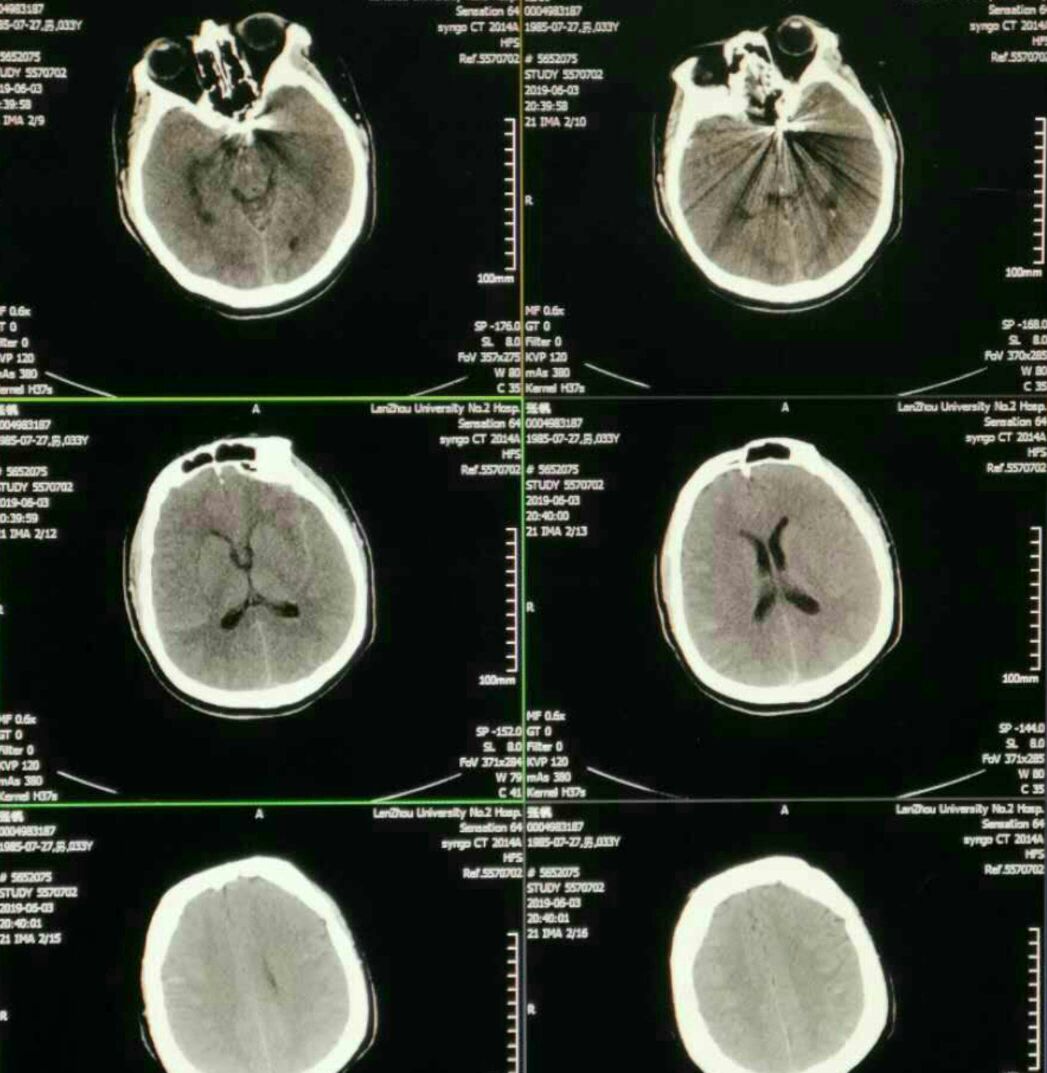

CT蛛网膜下腔出血

急查头颅CT无出血,左侧侧裂区疑似血栓影,即刻阿替普酶(体重80公斤)注入观察5分钟无果。决定二入导管室造影取栓。😓

果不其然,动脉瘤栓塞部位急性血栓形成波及同侧大脑中动脉闭塞导致左侧半球急性缺血表现。

次日复查CT无出血,可见左侧内囊膝部小梗(缺血不到1小时啊!),真是后怕😣